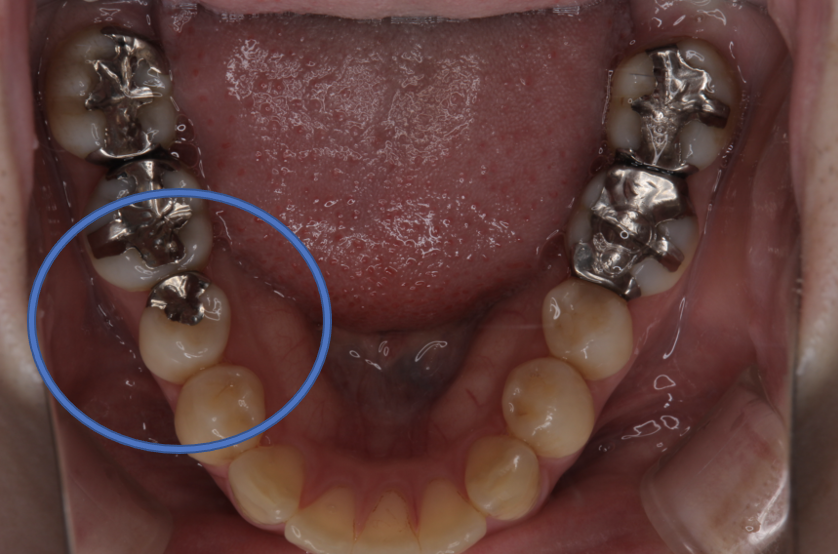

フルジルコニアIn 3 No.81

Before

After

| 治療方法 | フルジルコニアIn 虫歯などで失った歯質を天然歯と同じ色・質感のセラミックの一種であるジルコニア(人工ダイヤモンド)で補う治療法。 |

| 治療のデメリット | 変色がなく耐久性の高い治療ですが、歯周病や二次虫歯を予防するためには歯科医院での定期的なメインテナンスが大切です。 |

| 費用 | ¥69,000 |

| 通院回数 | 1ヶ月〜3ヶ月 |

| 備考 | 院長より 奥歯の、銀歯の中にむし歯が進行していたケースです。詰め物を選ぶ時には、見た目の自然さよりも、噛み合わせが強いことへの対応を 重視して、セラミックではなく、強度が強く人工ダイヤモンドとしても使用されるジルコニアインレーを選択することもあります。 |